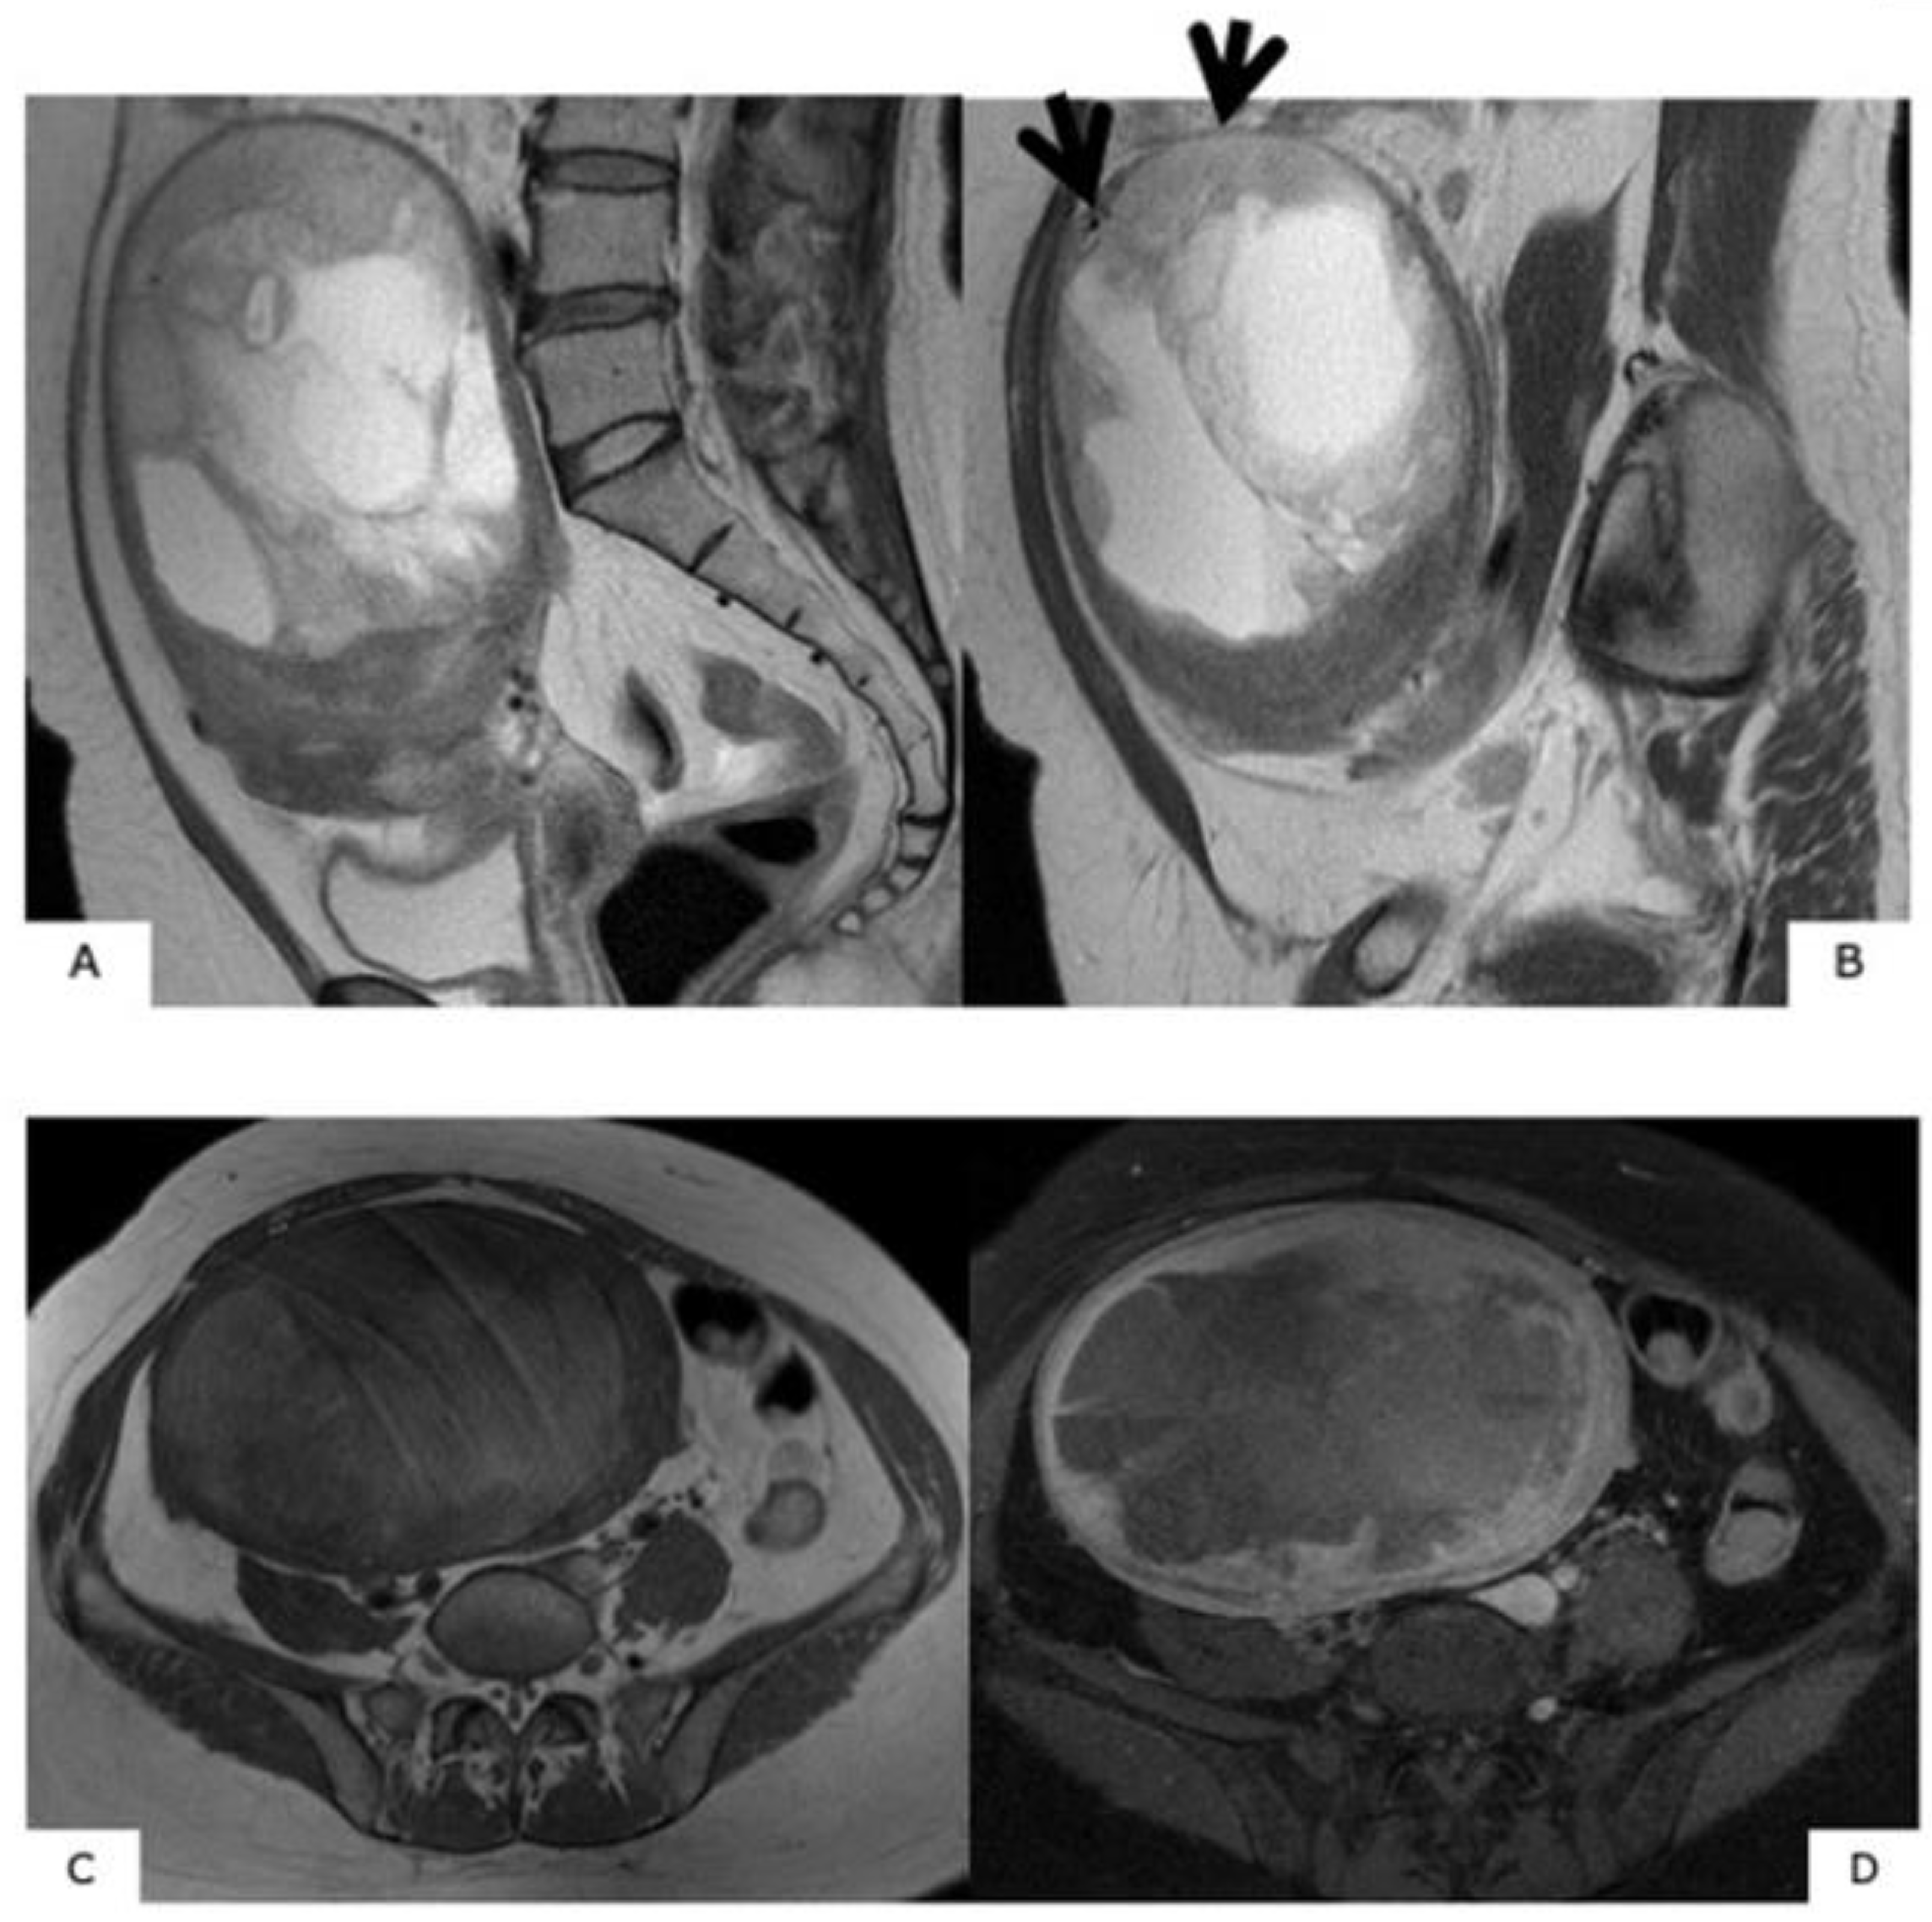

An MRI scan is useful in differentiating between uterine myoma and sarcoma because a typical MR image for myoma exists. That is, uterine myoma shows a clear border, with a mostly spherical shape. In T1WI, there are more equivalent signals or relatively low signals compared to those for normal muscle layer, and in T2WI, mass is depicted in signals that are patently lower than those for normal muscle layer (Figure 1). Confirmation of an MR image enables the diagnosis of myoma. However, when the modification of degeneration is added to a myoma, a completely different image finding is presented than the above-described typical one (Figure 2). Subsequently, the differentiation of such a myoma from uterine sarcoma becomes problematic.

Figure 1.

Typical images of uterine myoma in magnetic resonance images. In T1-weighted images, signals equivalent to or relatively lower than that of the normal myometrium can be observed. In T2-weighted images, signals that are clearly lower than those of the normal myometrium, with resection of almost all spherical masses with clearly defined borders, can be observed.